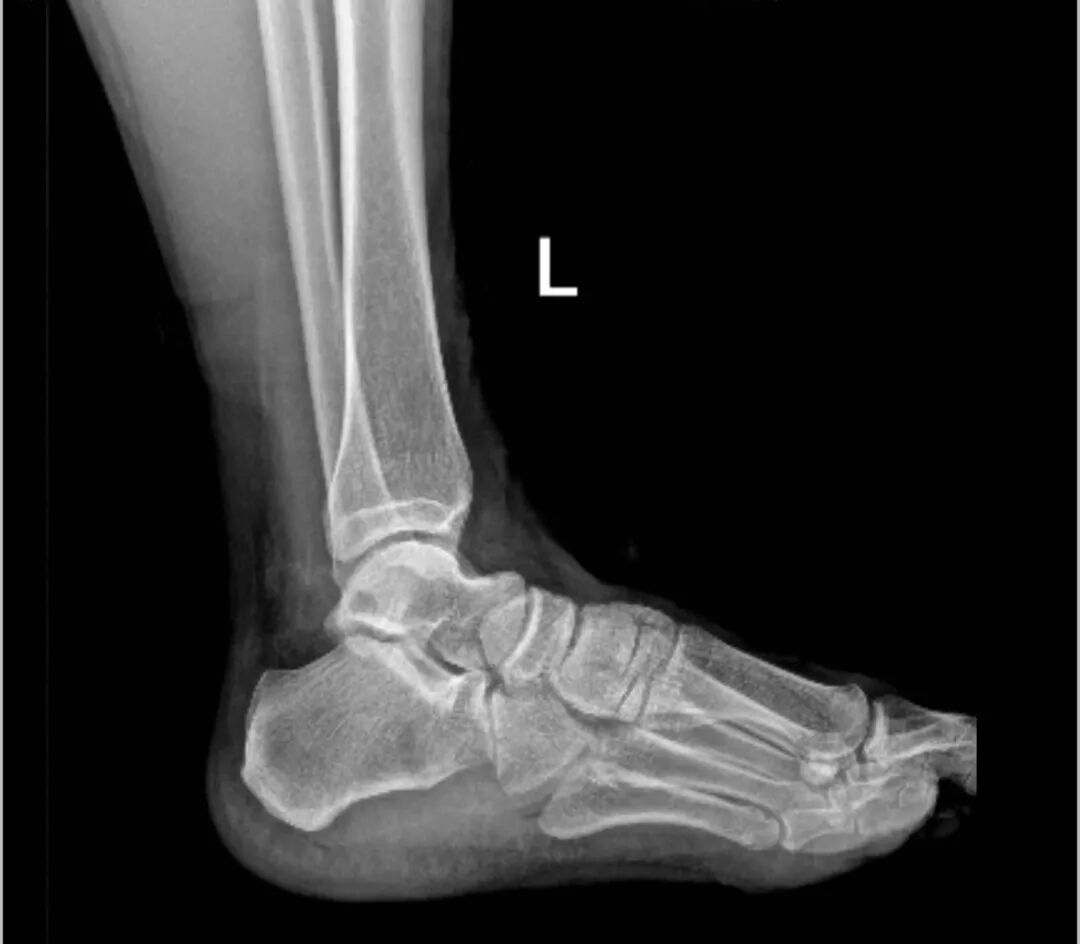

就在李大哥迷茫、纠结之际,偶然在网上看到了来自荆门市人民医院宣传视频——跟骨骨刺微创切除术。李大哥便立即联系发布视频的医生,几经辗转找到了该院关节外科的徐立副主任,起初通过电话问诊,但无法了解患者具体情况,徐立便提出微信好友申请,告知李大哥先在当地拍一张X片,以便了解具体位置、大小等。

▲李大哥脚后跟的“骨刺”